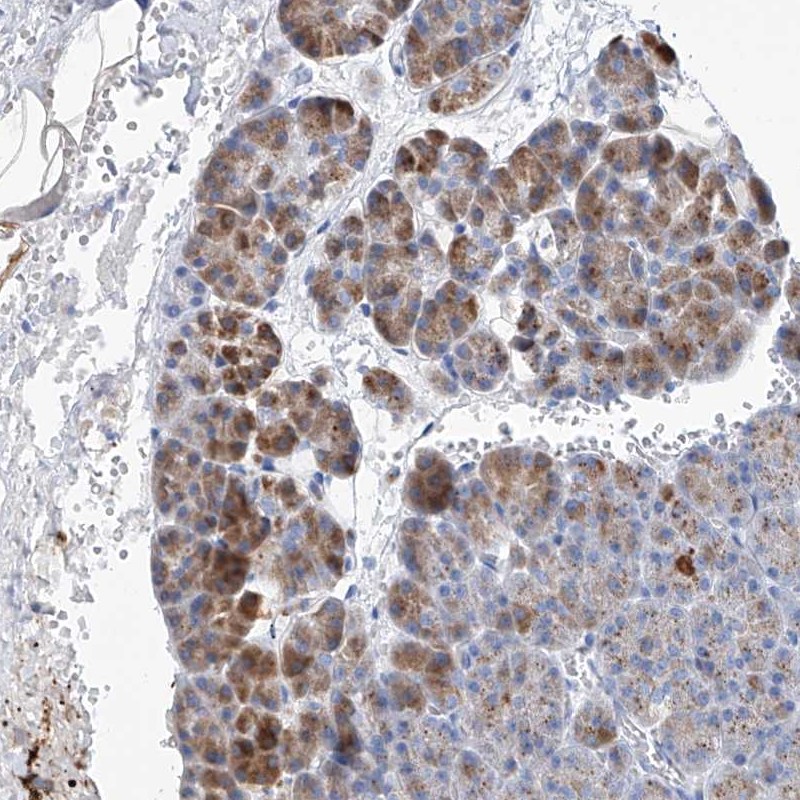

Immunohistochemical staining of human pancreas shows moderate cytoplasmic positivity in exocrine glandular cells.